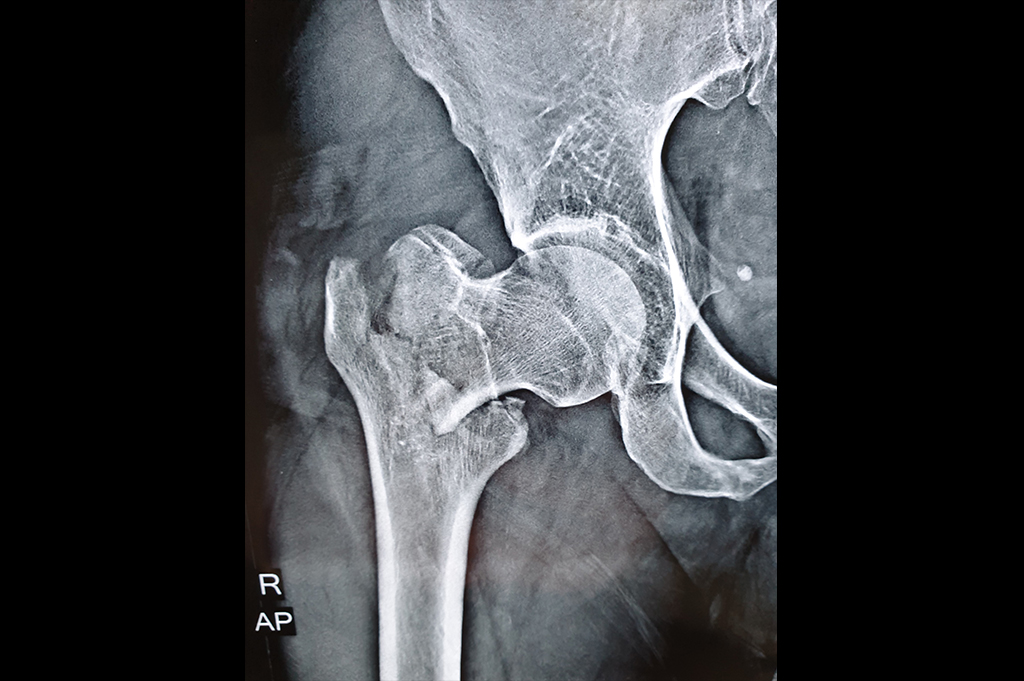

Intertrochanteric Fracture

Neck Femur Fracture